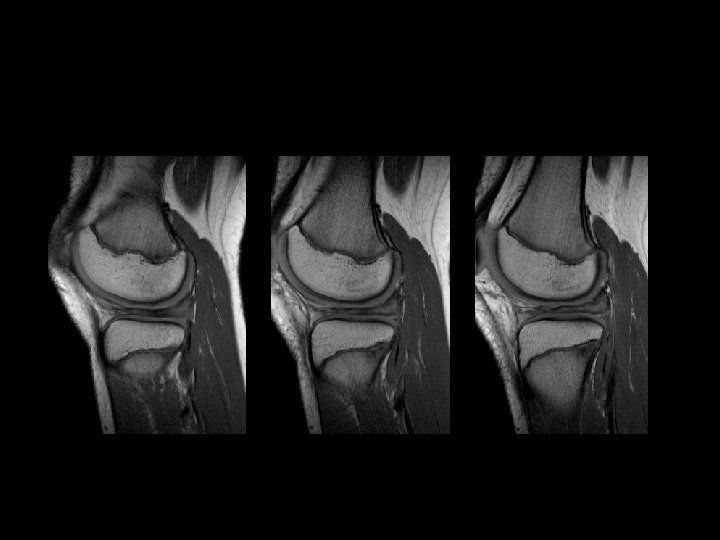

Ostéochondrites • Fréquence décroissante – – Condyle médial Condyle latéral Trochlée fémorale Rotule • Étiologie inconnue : micro traumatismes, traumatismes aigus, ischémie, facteurs génétiques • Juvénile / Adulte selon la maturité osseuse • Forme juvénile, meilleur pronostic

IRM � • Apprécier la stabilité du fragment • Cartilage articulaire • Intérêt des séquences « cartilage »

Critères pronostiques à l’IRM • Taille de la lésion +++++ • Liseré hyper intense ? ? ? • Kystes périlésionnels ?